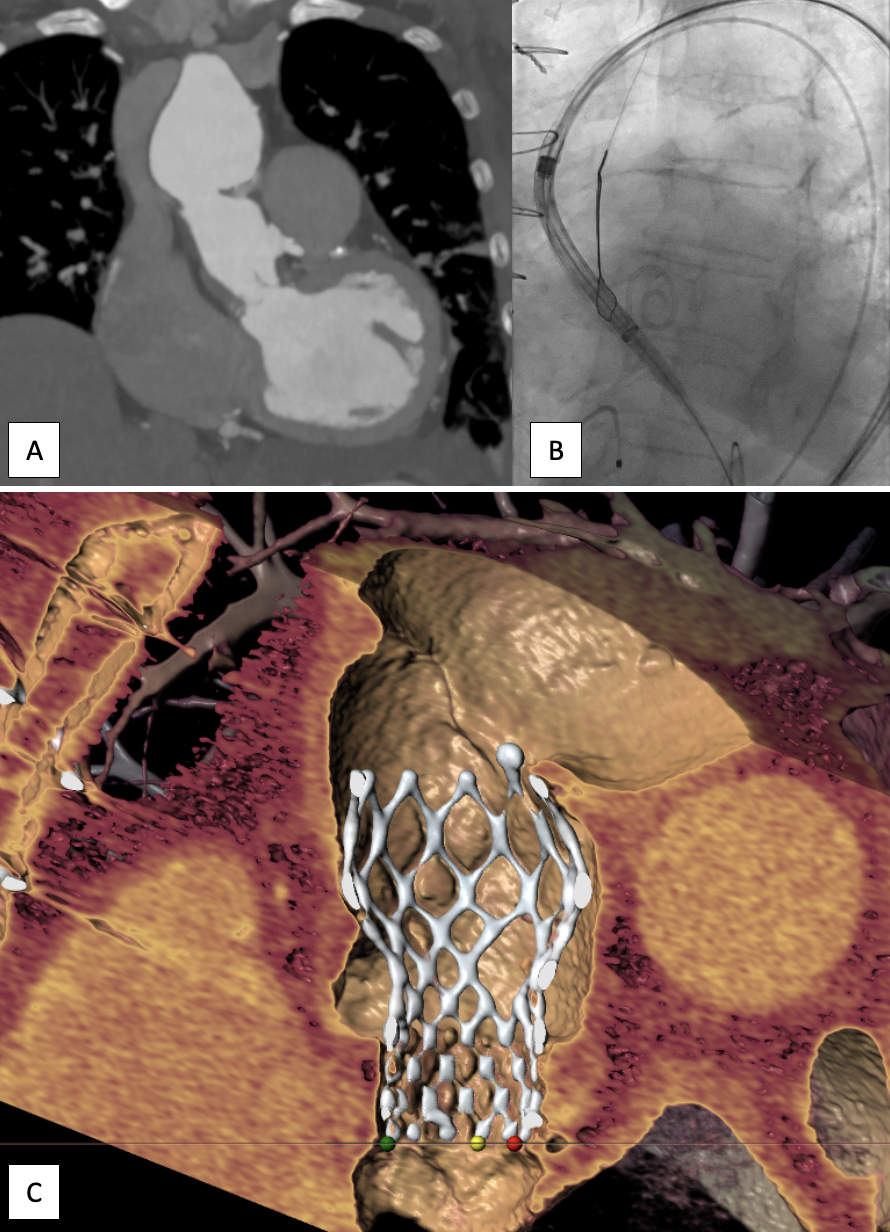

Background: Hemolytic anemia after surgical valve repair is rare but potentially life-threatening and is mostly described in the context of paravalvular regurgitation. Case Summary: A 78-year-old women with prior surgical mitral valve repair using ring annuloplasty and neochordae implantation presented with progressive fatigue, dyspnea and laboratory evidence of severe hemolytic anemia. Further laboratory work-up ruled out autoimmunhemolytic anemia. Transthoracic and transesophageal echocardiography revealed severe eccentric, valvular mitral regurgitation caused by anterior leaflet prolapse with a high-velocity regurgitant jet striking the annuloplasty ring. The patient underwent successful transcatheter mitral edge-to-edge repair (M-TEER), achieving reduction of mitral regurgitation to mild and resolution of hemolysis. Discussion: This case highlights the importance of hemolysis due to valvular regurgitation as rare complication after surgical mitral valve repair and the utility of M-TEER as a re-do strategy for patients at prohibitive surgical risk. Take-Home Message: M-TEER is a safe and effective option for managing hemolytic anemia induced by recurrent MR after surgical repair. Besides paravalvular regurgitation, valvular regurgitation in the context of prior surgical MV repair should be recognized as a potential cause of hemolytic anemia.